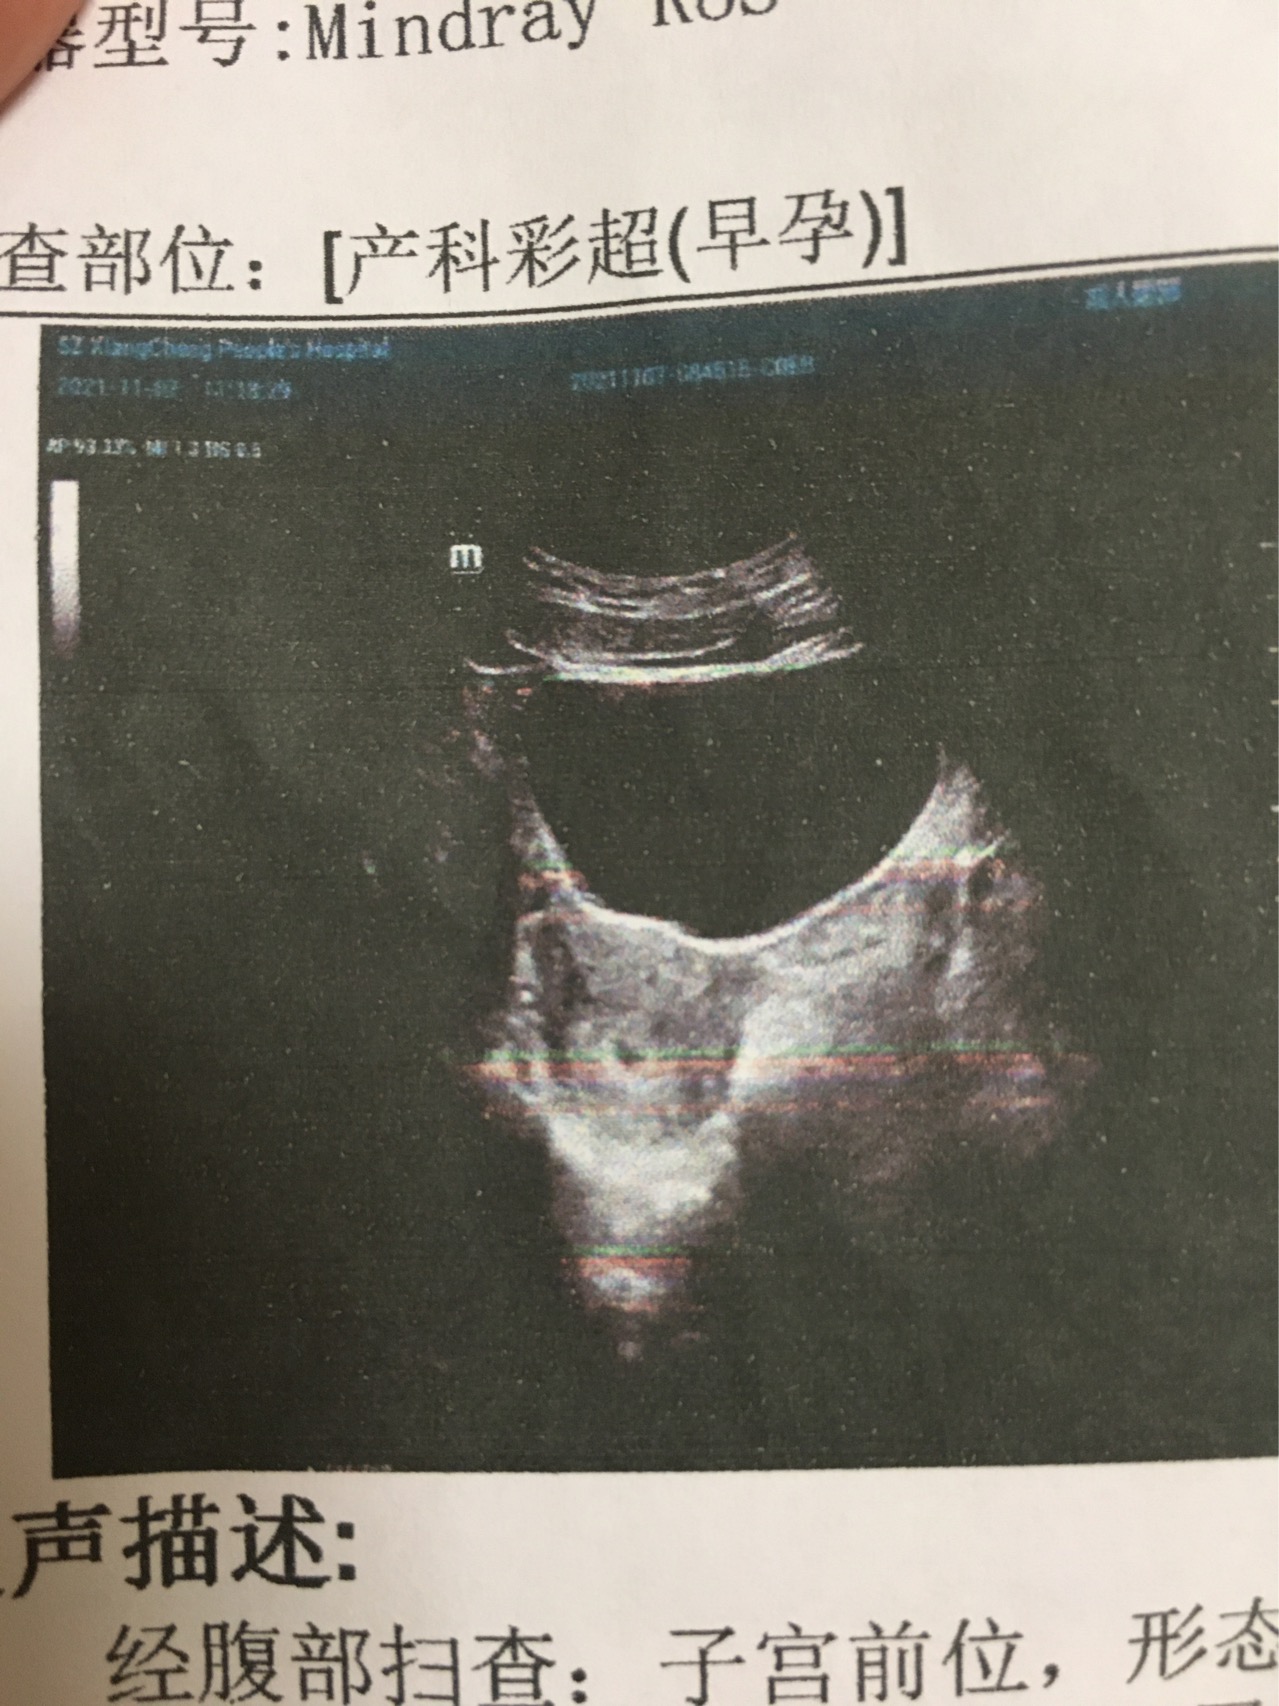

医生麻烦帮忙看看报告是否正常有地中海贫血吗